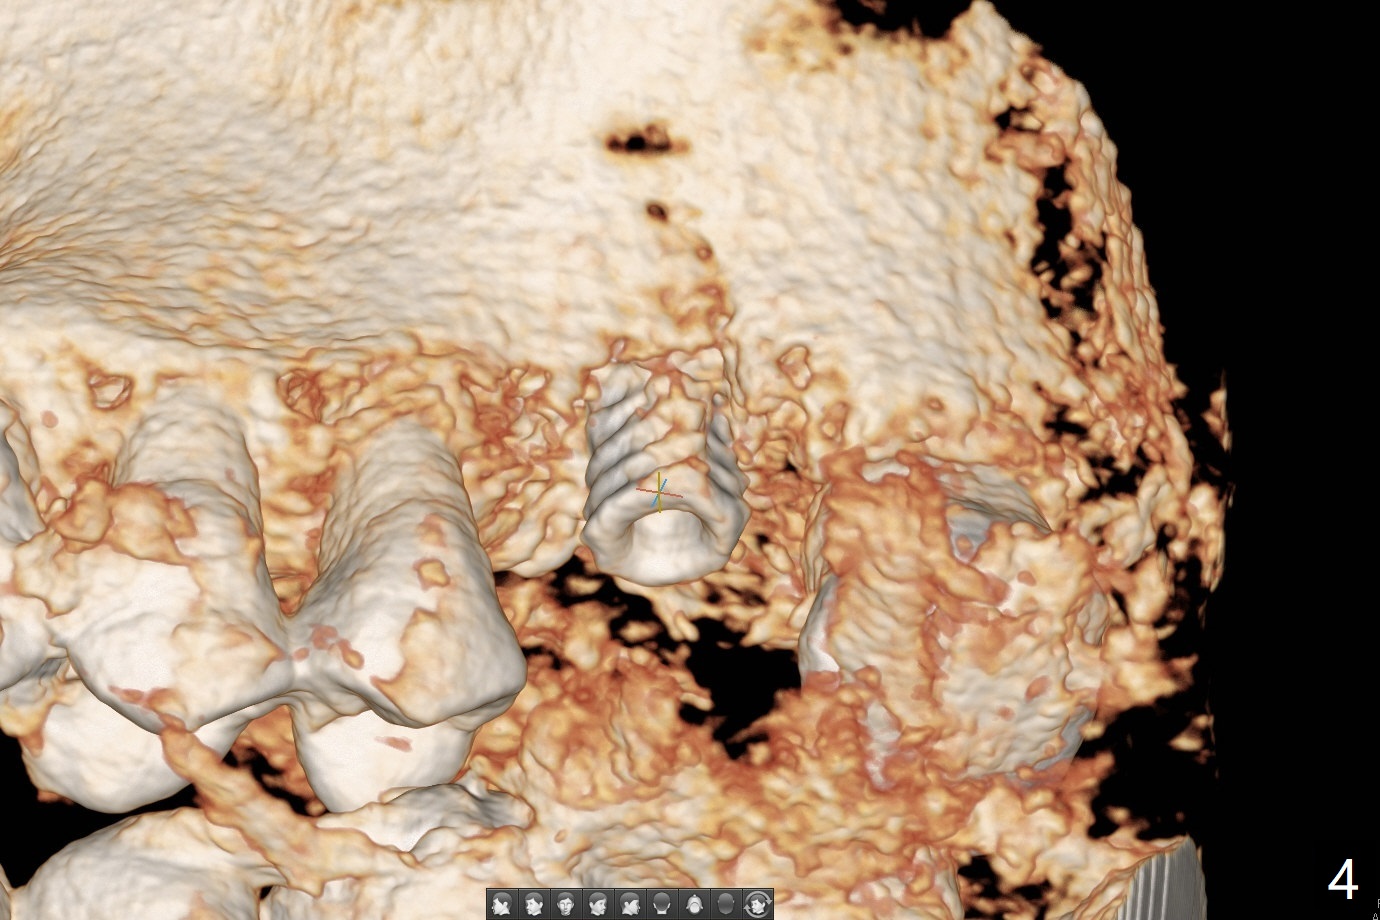

A 57-year-old woman complains of bad smell while use of water flosser between 11 and 21 months post cementation of implant crown at #14 (Fig.1,2). Bone loss is more obvious with CBCT (Fig.3,4), in spite of apparently normal gingiva around the implant after removal of the abutment and crown (Fig.5). In fact the buccal (B) gingiva is fragile with easy access to the underlying implant plateau. Following flap elevation, the bone loss is evident (Fig.6), but the implant plateau is slightly subcrestal (Fig.7 *). The exposed implant threads are covered with the 1st round of bone graft (Fig.8). After 2nd round of allograft (Fig.10-12) and collagen membrane, the flaps are approximated (Fig.9). The wound is covered by acrylic dressing. The latter is loose, but stays in place 1 week postop (Fig.13). Due to short neighboring teeth, the acrylic dressing is able to be removed with wiggling; it appears that the wound is healing (Fig.14). The dressing returns for another 2 weeks; some of the graft has been lost (Fig.15). The dressing does not return 7 weeks postop, since the wound is healing (Fig.16).